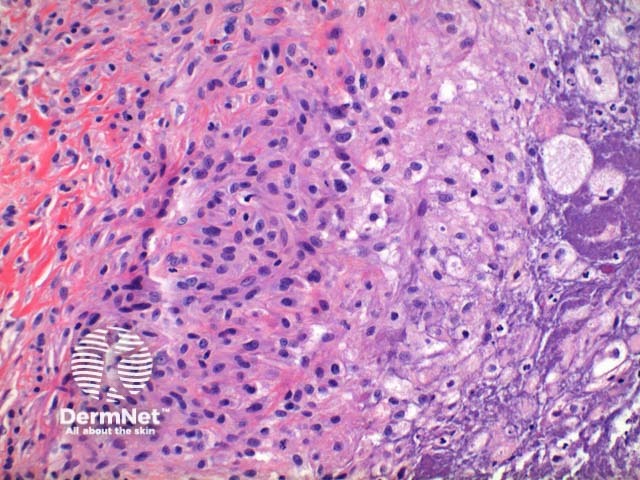

Scanning power view of phaeohyphomycosis shows a deeply extending granulomatous pattern (Figure 1) which may show areas of necrosis (Figure 2). Centrally an abscess or cystic nodule may form. Frequently a foreign body such as a wood splinter can be seen. The epidermis commonly shows pseudoepitheliomatous hyperplasia. The inflammatory infiltrate is comprised of histiocytes with multinucleated giant cells, and numerous neutrophils (Figures 3,4 and 5). At high power branching septate pigmented fungal hyphae can be seen (Figure 6).

Figure 1